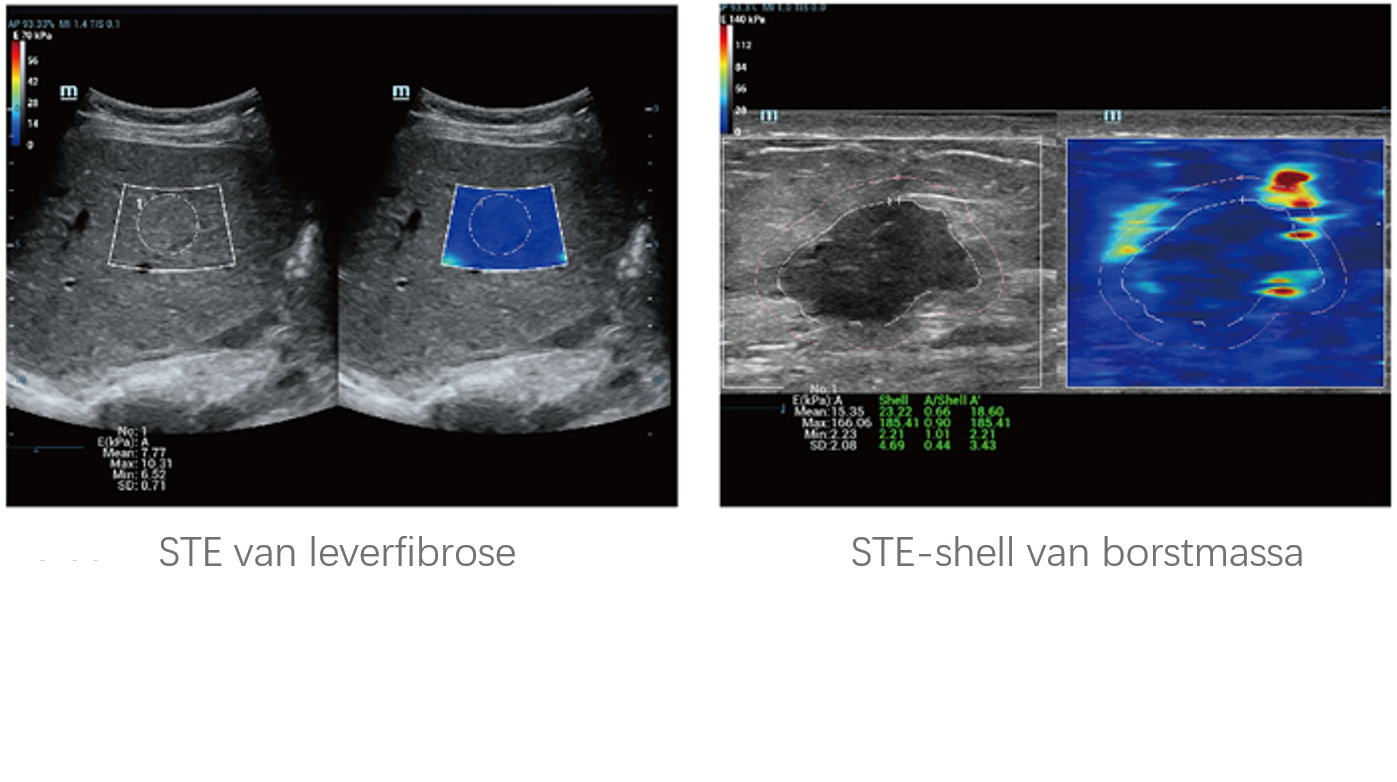

Sinds de oprichting van het bedrijf is Mindray voortdurend op zoek naar nieuwe manieren om het diagnostisch vertrouwen te vergroten. Resona 7 wordt aangestuurd door de meest revolutionaire ZONE Sonography?-technologie. Zijn nieuwe ZST+-tilt de kwaliteit van ultrasoundbeeldvorming naar een hoger niveau door middel van zoneacquisitie en kanaalgegevensverwerking.

Naast de hoogwaardige beeldvormingskwaliteit verbetert de Resona 7 tevens de klinische onderzoeksmogelijkheden met de revolutionaire V Flow voor vasculaire hemodynamische evaluatie, en de intelligentste vlakacquisitie van een 3D-gegevenssets voor de diagnose van het foetale, centrale zenuwstelsel. Met zijn combinatie van de meest intu?tieve, op vingerbewegingen gebaseerde multi-aanrakingsbediening en alle essenti?le klinische functies loopt de Resona 7 voorop in de nieuwe golven van ultrasoundinnovatie.